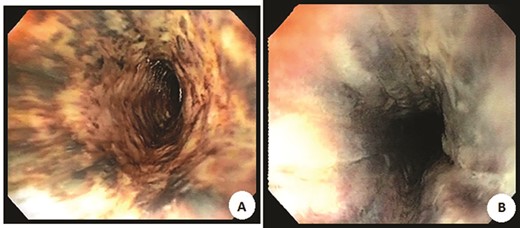

After the case was discussed with multiple teams and deemed too unsafe for surgery, the patient was admitted to the intensive care unit, bilateral thrombolytic catheters were placed from the legs to above the IVC, and he was treated with intravascular thrombolytic (Alteplase and Heparin) therapy (Fig. 3). On Day 5, he developed bloody emesis and was noted to have a hemoglobin drop from 12 to 8 g despite blood transfusions. The patient was resuscitated, and an EGD demonstrated a blackened esophagus of the entire esophagus with no involvement into the stomach (Fig. 4). Considering these findings, transthoracic echocardiogram (TTE) and chest computed tomography (CT) angiogram (CTA) were performed, which revealed patent foramen ovale (PFO) with small right to left shunt and an edematous esophagus and duodenum with no perforation or arterial inflow problem, respectively. No intervention was performed. The patient eventually stabilized and a repeat EGD a week later showed resolution of the ischemic esophagus. Patient was started back on liquid diet, which was advanced to solid diet and was discharged a week later.

Endoscopic images of the proximal (A) and distal (B) black esophagus.

AEN ‘black esophagus’ is a rare life-threatening condition characterized by circumferential black appearing friable esophageal mucosa involving various length of the esophagus [1, 3]. Most commonly is affecting the distal esophagus, however few cases reported proximal esophagus [3]. Endoscopic appearance is diagnostic, and biopsies are not necessary unless if infectious causes are suspicious. The pattern of insult is unique ‘inside out’ and may involve full thickness of the esophagus, so close monitoring is the key.

In this case, we have described a unique presentation of black esophagus few days after the patient did receive intravascular thrombolytic. Patient developed hematemesis, dizziness and hypotension. Multiple studies have shown a combination of multiple factors behind the development of the black esophagus. Our patient underwent EGD, which revealed a necrotic mucosa circumferentially from just below the upper esophageal sphincter stopping exactly at the GE junction. The stomach was completely normal. It was felt that this may be ischemic in etiology. A TTE showed PFO with a small right to left shunting. CTA of the chest revealed thickened and edematous esophagus. The similar findings are thicken and edematous duodenum from the CTA. No obvious etiology could be identified. The question being asked is whether he has had embolization into the esophageal arterial supply. This would be extremely unusual, particularly given that there is some duodenal involvement as well. Intra-arterial thrombosis of the esophageal vessels in the setting of PFO with thrombolytic therapy could be considered. To date, there are no known treatments for black esophagus. The current recommendation is to intensively treat the patient’s comorbidities, optimize vascular perfusion, aggressively suppress acid production and treat esophageal infections, if present [3, 4]. The overall mortality in the largest case review to date was 32%. The high mortality was most frequently secondary to the seriousness of comorbid disease states. The mortality secondary to esophageal disease alone was 6% [1, 3].